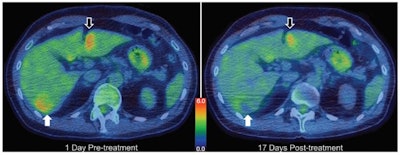

Treatment planning, modeling, and example results from a 50-year-old man with diffuse multilobular hepatocellular carcinoma in segment VI. Axial F-18 FDG PET/CT images obtained one day before (left) and 17 days after (right) treatment. Total lesion glycolysis of target tumor (white arrows) decreased by 36.4%, whereas there was no substantial change over the volume of a similarly sized tumor that received drug but no focused ultrasound (black arrows). Color bar indicates standardized uptake value. Images courtesy of  Michael Gray, PhD, et al, Radiology.

To assess therapeutic response, the team imaged all participants before and after treatment using contrast-enhanced MRI and CT and also FDG-PET/CT. In the first patient, PET revealed a 36.4% reduction in total lesion glycolysis of the target tumor, whereas there was no substantial response in a similarly sized tumor that received drug but no focused ultrasound. In six of the 10 participants, partial responses were seen after just one treatment cycle.